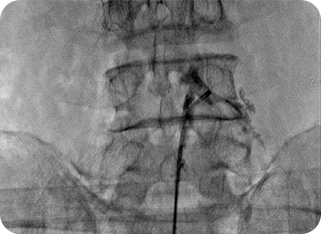

2

신경성형술(PEN)

가느다란 특수 카테터를 삽입해 유착된 신경을 풀어주고 약물을 주입하는 방식입니다.

절개 없이 진행되며, 만성 통증 환자에게 효과적입니다.

풍선확장술 사진1

풍선확장술 사진2

3

풍선확장술

미세한 풍선을 신경관이나 협착 부위에 삽입해 좁아진 공간을 확장시킨 뒤

약물을 투여합니다. 신경 압박을 줄이고 혈류를 개선하여 통증 완화와

기능 회복에 도움을 줍니다.